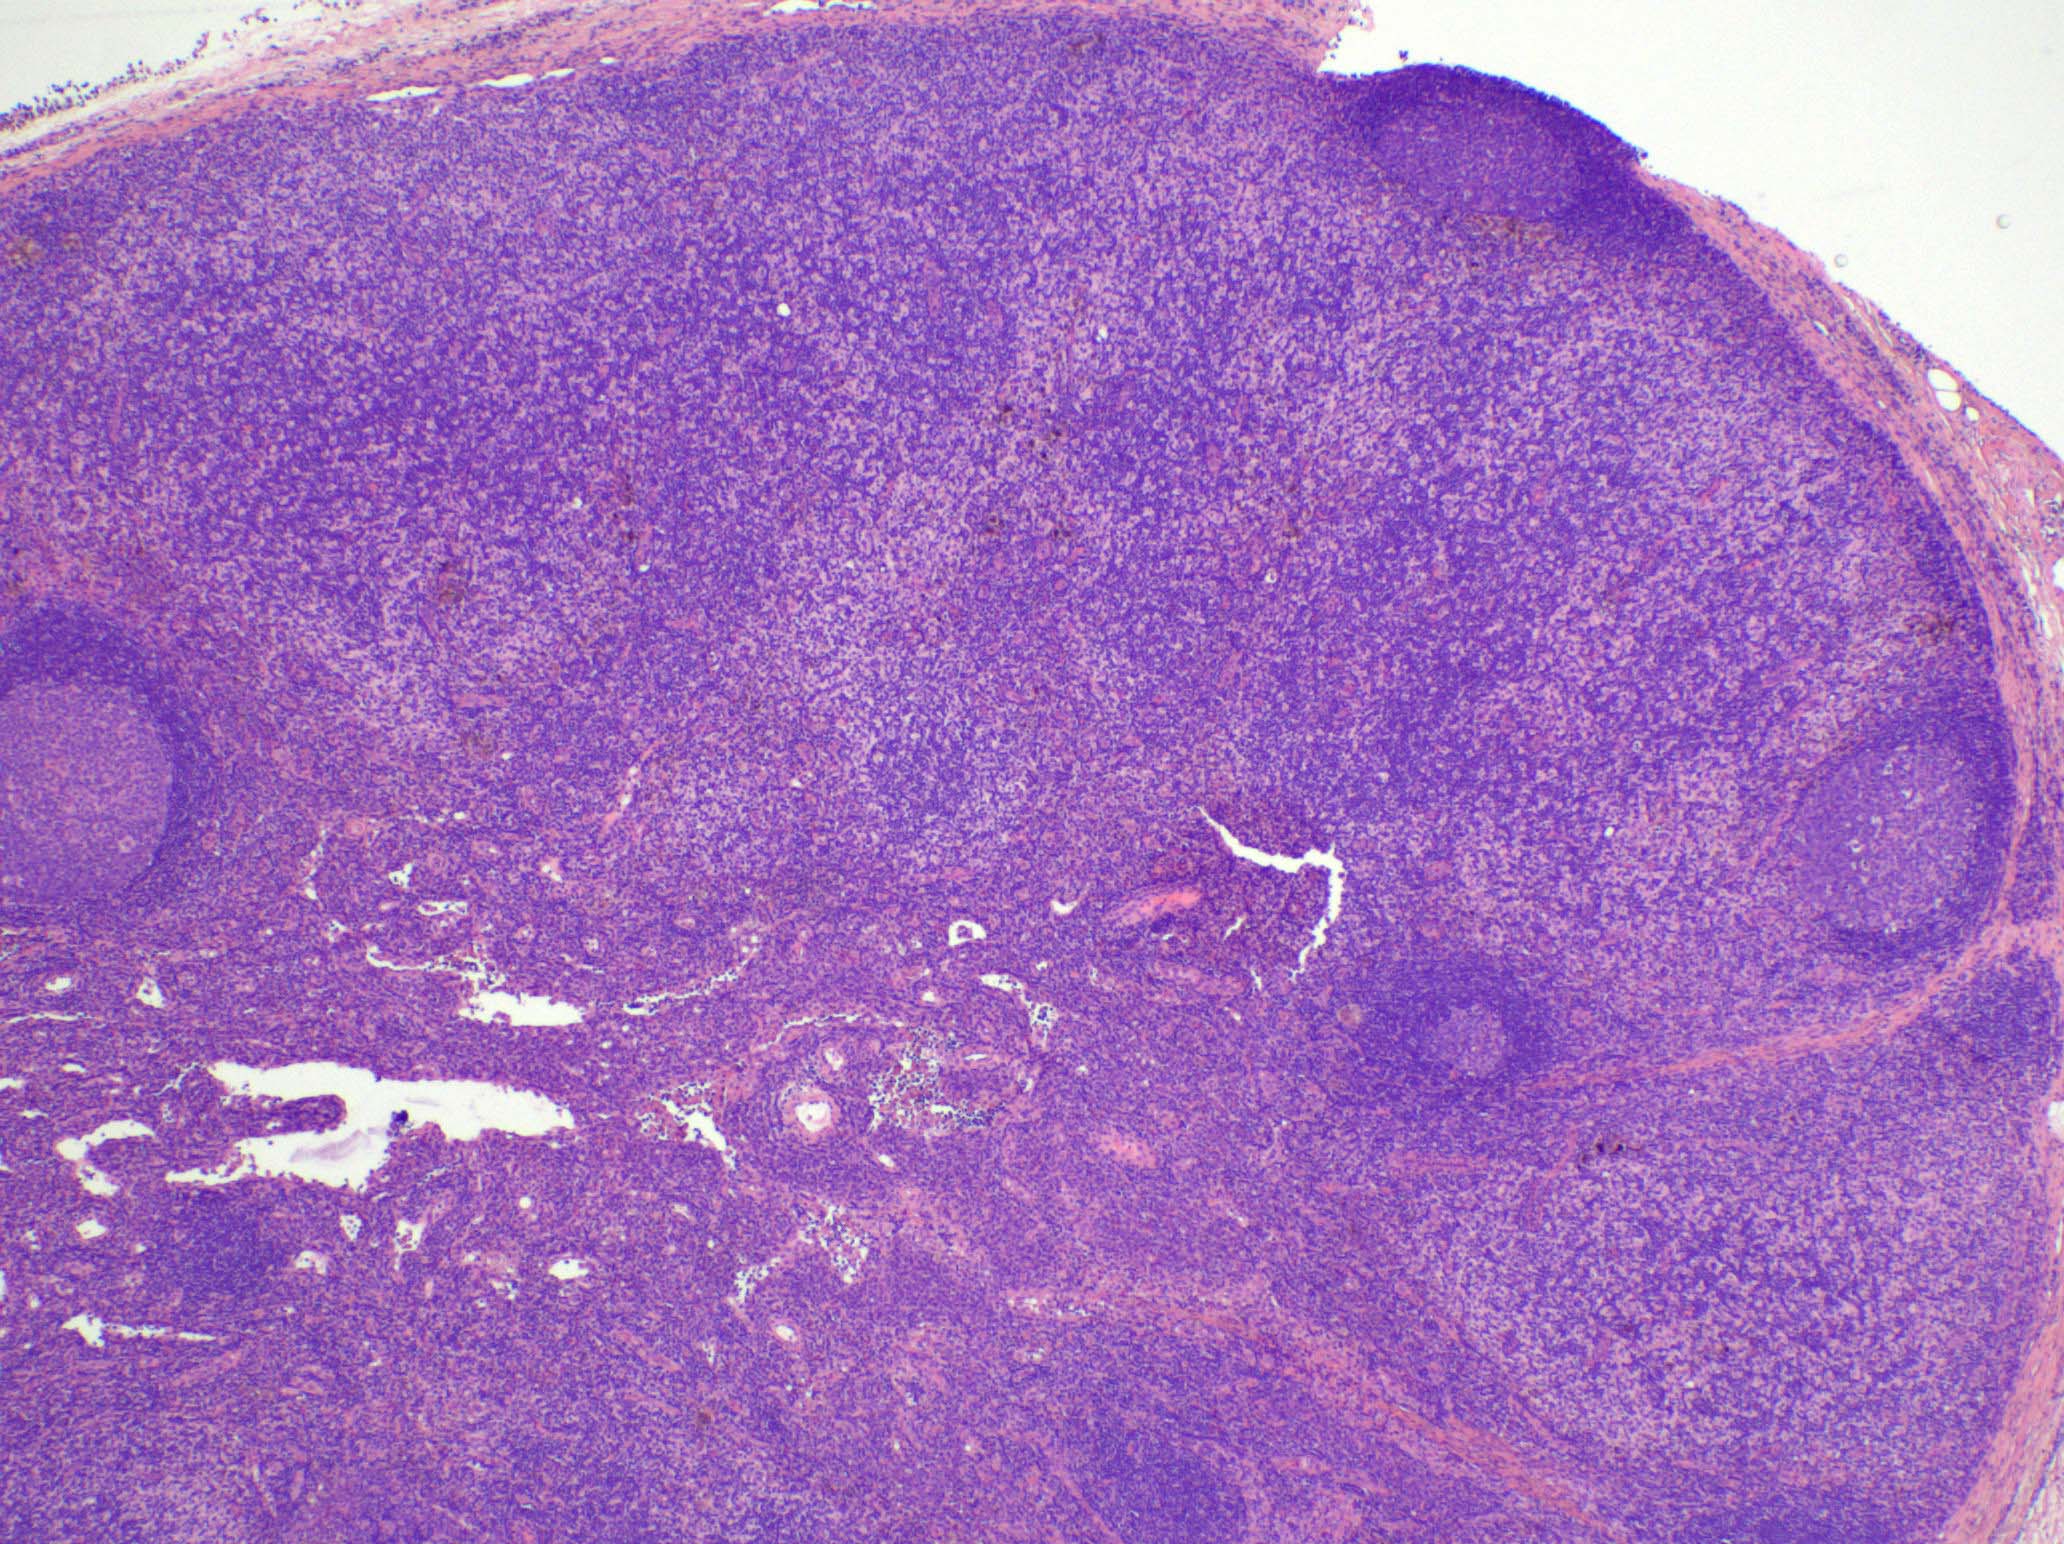

Microscopic (histologic) images

Contributed by Ingrid Tam, M.D., M.Sc., Emina Emilia Torlakovic, M.D., Ph.D. and Nikhil Sangle, M.D. (Case #396)

- Severe / florid

- Large vague nodules or sheets of interdigitating dendritic cells that can compress lymphoid follicles

- Rarely, sinuses can be partially compressed

- Severe forms are more frequently seen in patients with mycosis fungoides